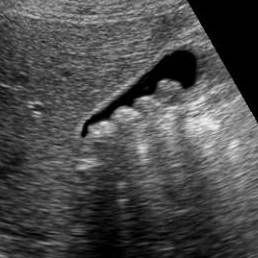

Наиболее распространенный метод выявления этого заболевания – ультразвуковое исследование. Благодаря современной аппаратуре и опыту врачей клиники ЦЭЛТ, его результатов хватает для уверенной установки диагноза. Но иногда в качестве дополнительных методов применяется ретроградная панкреатохолангиорентгенография и МР-холангиография.